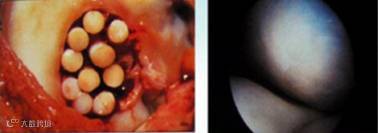

图 透明软骨

术后(左)及术后5年(右)对比图